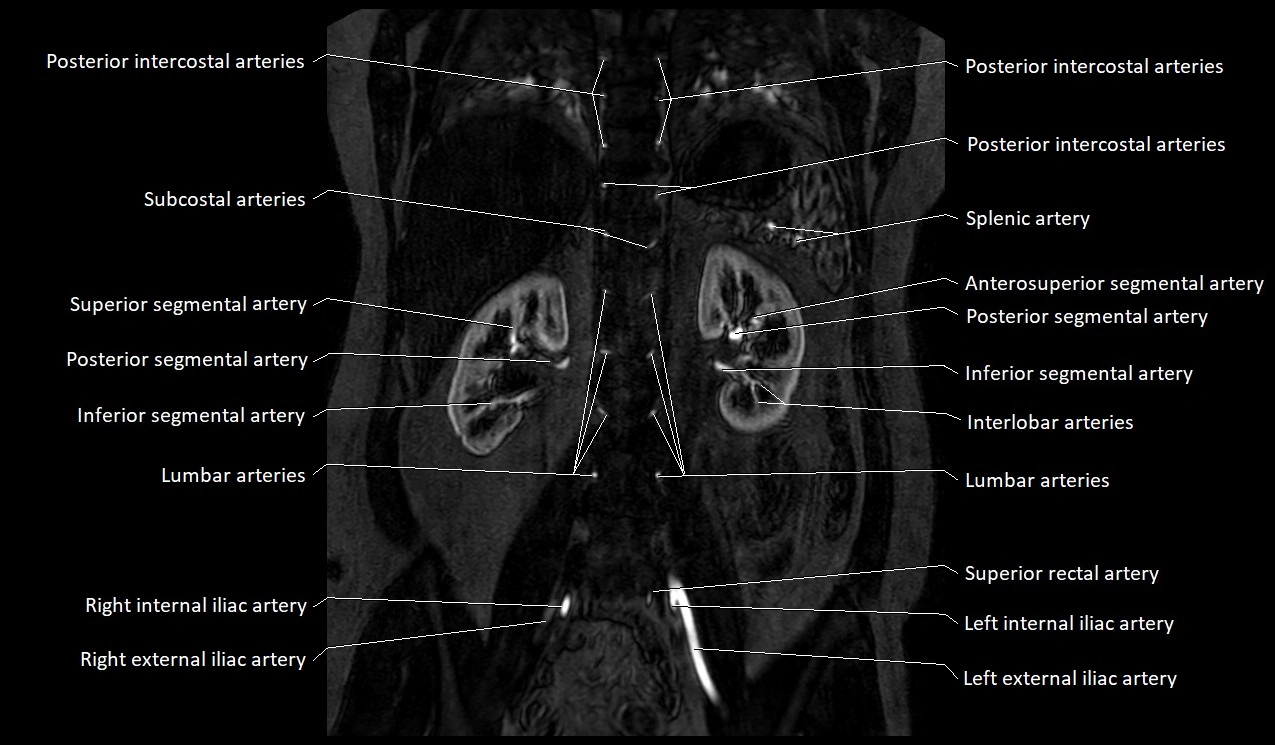

MRI Appearance

T1-weighted images:

Artery appears as a small linear hypointense flow void coursing over the superior pubic ramus

Seen within bright perivascular fat of pelvis

MRA Pelvis with Gadolinium:

Clearly delineates the origin, course, and anastomoses of the accessory obturator artery

Identifies connection with inferior epigastric artery, external iliac artery, or obturator artery

Excellent for detecting vascular variants prior to surgery

Useful in mapping pelvic vasculature in trauma, tumor embolization, or preoperative planning